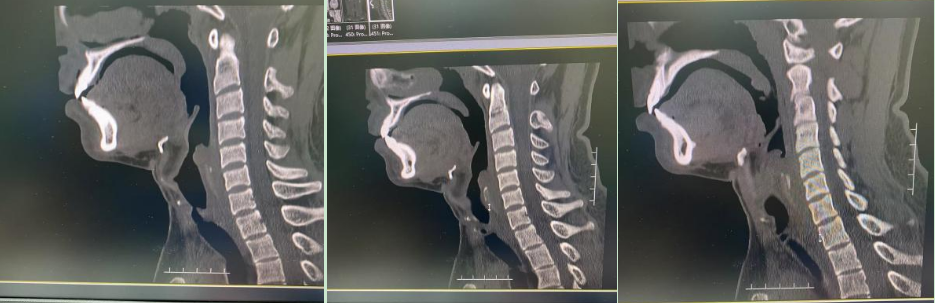

一、病情回顾:气道肉芽增生、手术遇阻 患者男性、20岁,因脑外伤在中信惠州医院救治。患者气管切口虽早已愈合,但言语声音低弱表述不清,休息状态下呼吸喘鸣声明显,稍有活动时呼吸喘鸣声更明显。医学影像中心喉部CT平扫+三维重建显示:1.喉咽左后壁肿胀增厚,相应喉腔变窄。2.环状软骨多发骨折,气管腔塌陷、变形且变窄。这些状况严重阻碍了患者的呼吸,使得即将进行的神经外科手术面临较大风险。 二、冷冻冻切+高压球囊协同“作战”,“抢修”生命通道 面对复杂紧急病情,呼吸医学中心介入团队迅速制定了详细的治疗方案。行无痛支气管镜检查和辅助喉罩通气术,术中迅速冻切肉芽组织,遂即患者呼吸的皮氧饱和度从60%升至正常范围。 卢晔教授表示,患者仰卧时呼吸困难,且术前三维重建发现肉芽组织“疯长”堵塞大气道,严重影响后续手术安全进行。为此,团队决定采取反复多次高压球囊扩张 + 反复冷冻冻切肉芽组织 + 冻融新鲜撕裂口的治疗方式。术中,利用冷冻冻切技术,短短几分钟内就将肉芽组织快速清除,使气道迅速达到基本通畅。同时,根据患者疤痕狭窄的程度和部位,精准选择不同直径、不同压力的球囊,进行恰到好处的扩张,确保手术安全。这项技术具有诸多显著优势。操作简便,易于学习掌握;重复性良好,能够根据患者具体情况灵活运用;损伤小,安全性高,可有效避免中央气道气肿和气胸的发生,对于疤痕致狭窄也不会引发大出血,为患者的治疗提供了有力保障。

影像图像